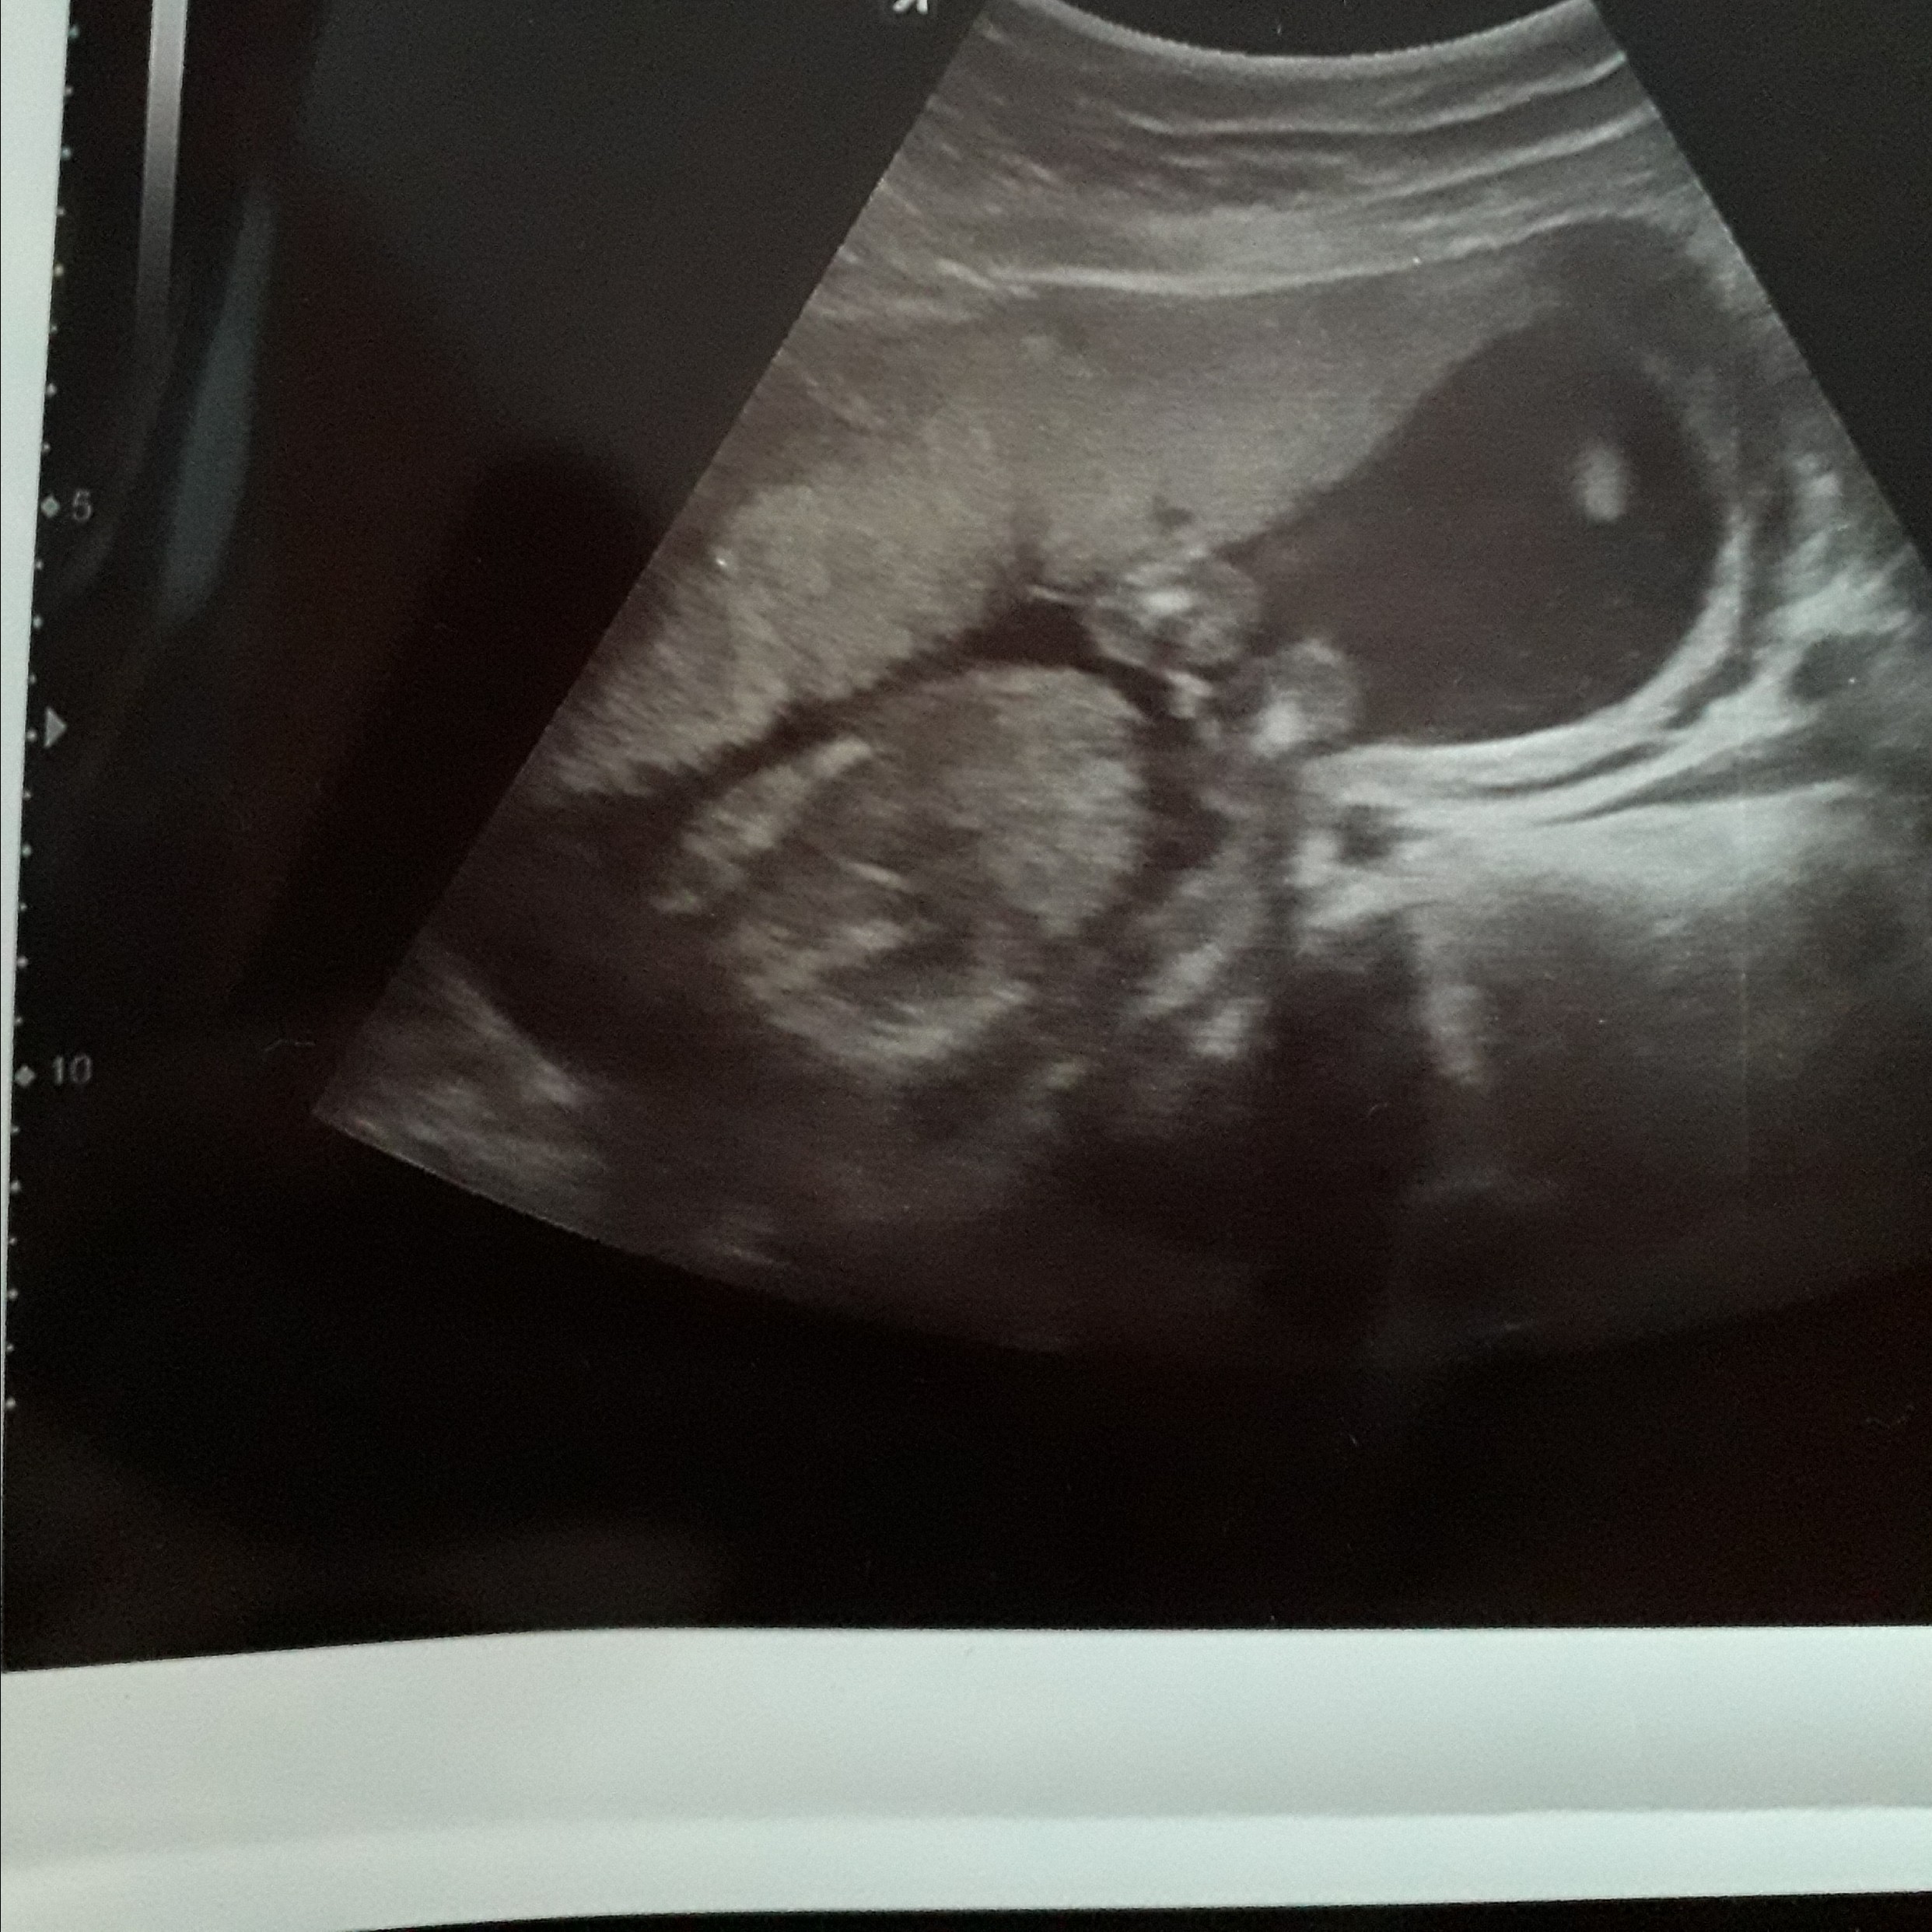

Witam w 19 tygodniu ciąży dowiedziałam się ze będę miała dziewczynkę w 20 tyg okazało się jednak , że to chłopak. Sama już nie wiem bo na jednym usg widać na pewno dziewuche a na drugim chłopca. Może to pempowina ?? Może ktoś mi pomoże rozwiązać ta zagadkę